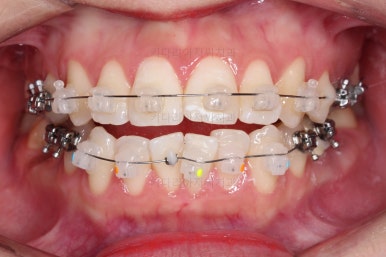

장치를 부착해서 가지런하게 하고요.

발치가 필요한 치아를 하나씩 뽑아나갑니다.

어금니 발치 공간이 어마어마하게 넓죠?

저 공간만큼 앞니가 들어가도록 하면 큰일납니다. 입이 너무 많이 들어가게 됩니다.

따라서 매우 신중한 테크닉으로 입매 조절을 잘 해야 합니다.

이번 부산사랑니교정 환자분이 선택하신 장치는 데이몬 클리어라고 하는 자가결찰 세라믹 장치인데요.

현존하는 세라믹 장치 중에 가장 심미적인 장치입니다.

철사를 잡아주는 뚜껑은 금속으로 되어있는 클리피씨나 엠파워 클리어에 비해 뚜껑까지도 세라믹으로 되어있기 때문이죠.

대신 금속 성분이 많은 장치보다는 부피가 확실히 커지게 되는데요.

돌출입의 경우 초반에는 입이 더 나와보일 수 있고요.

입이 더 나오는 정도는 사람마다 매우 차이가 큽니다.

참고만 해주세요.